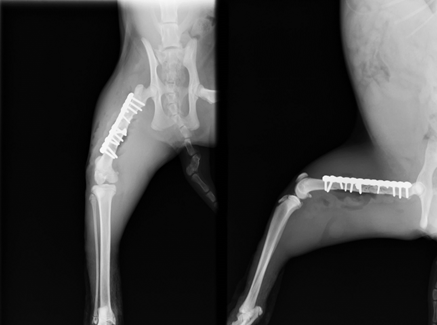

リコンストラクションプレート、ラグスクリューを使用し固定しました。

術後レントゲン しっかり固定されています。

術後は4日程で歩行可能となり、術後2週目で抜糸、完全に歩行も改善し完治としました。外に行く猫ちゃんは交通事故など多いためなかなか予防は難しいですが、手術して完全に良くなるのを見るとほんと嬉しくなります。この猫ちゃんもよくなってよかったですね(^0^)!